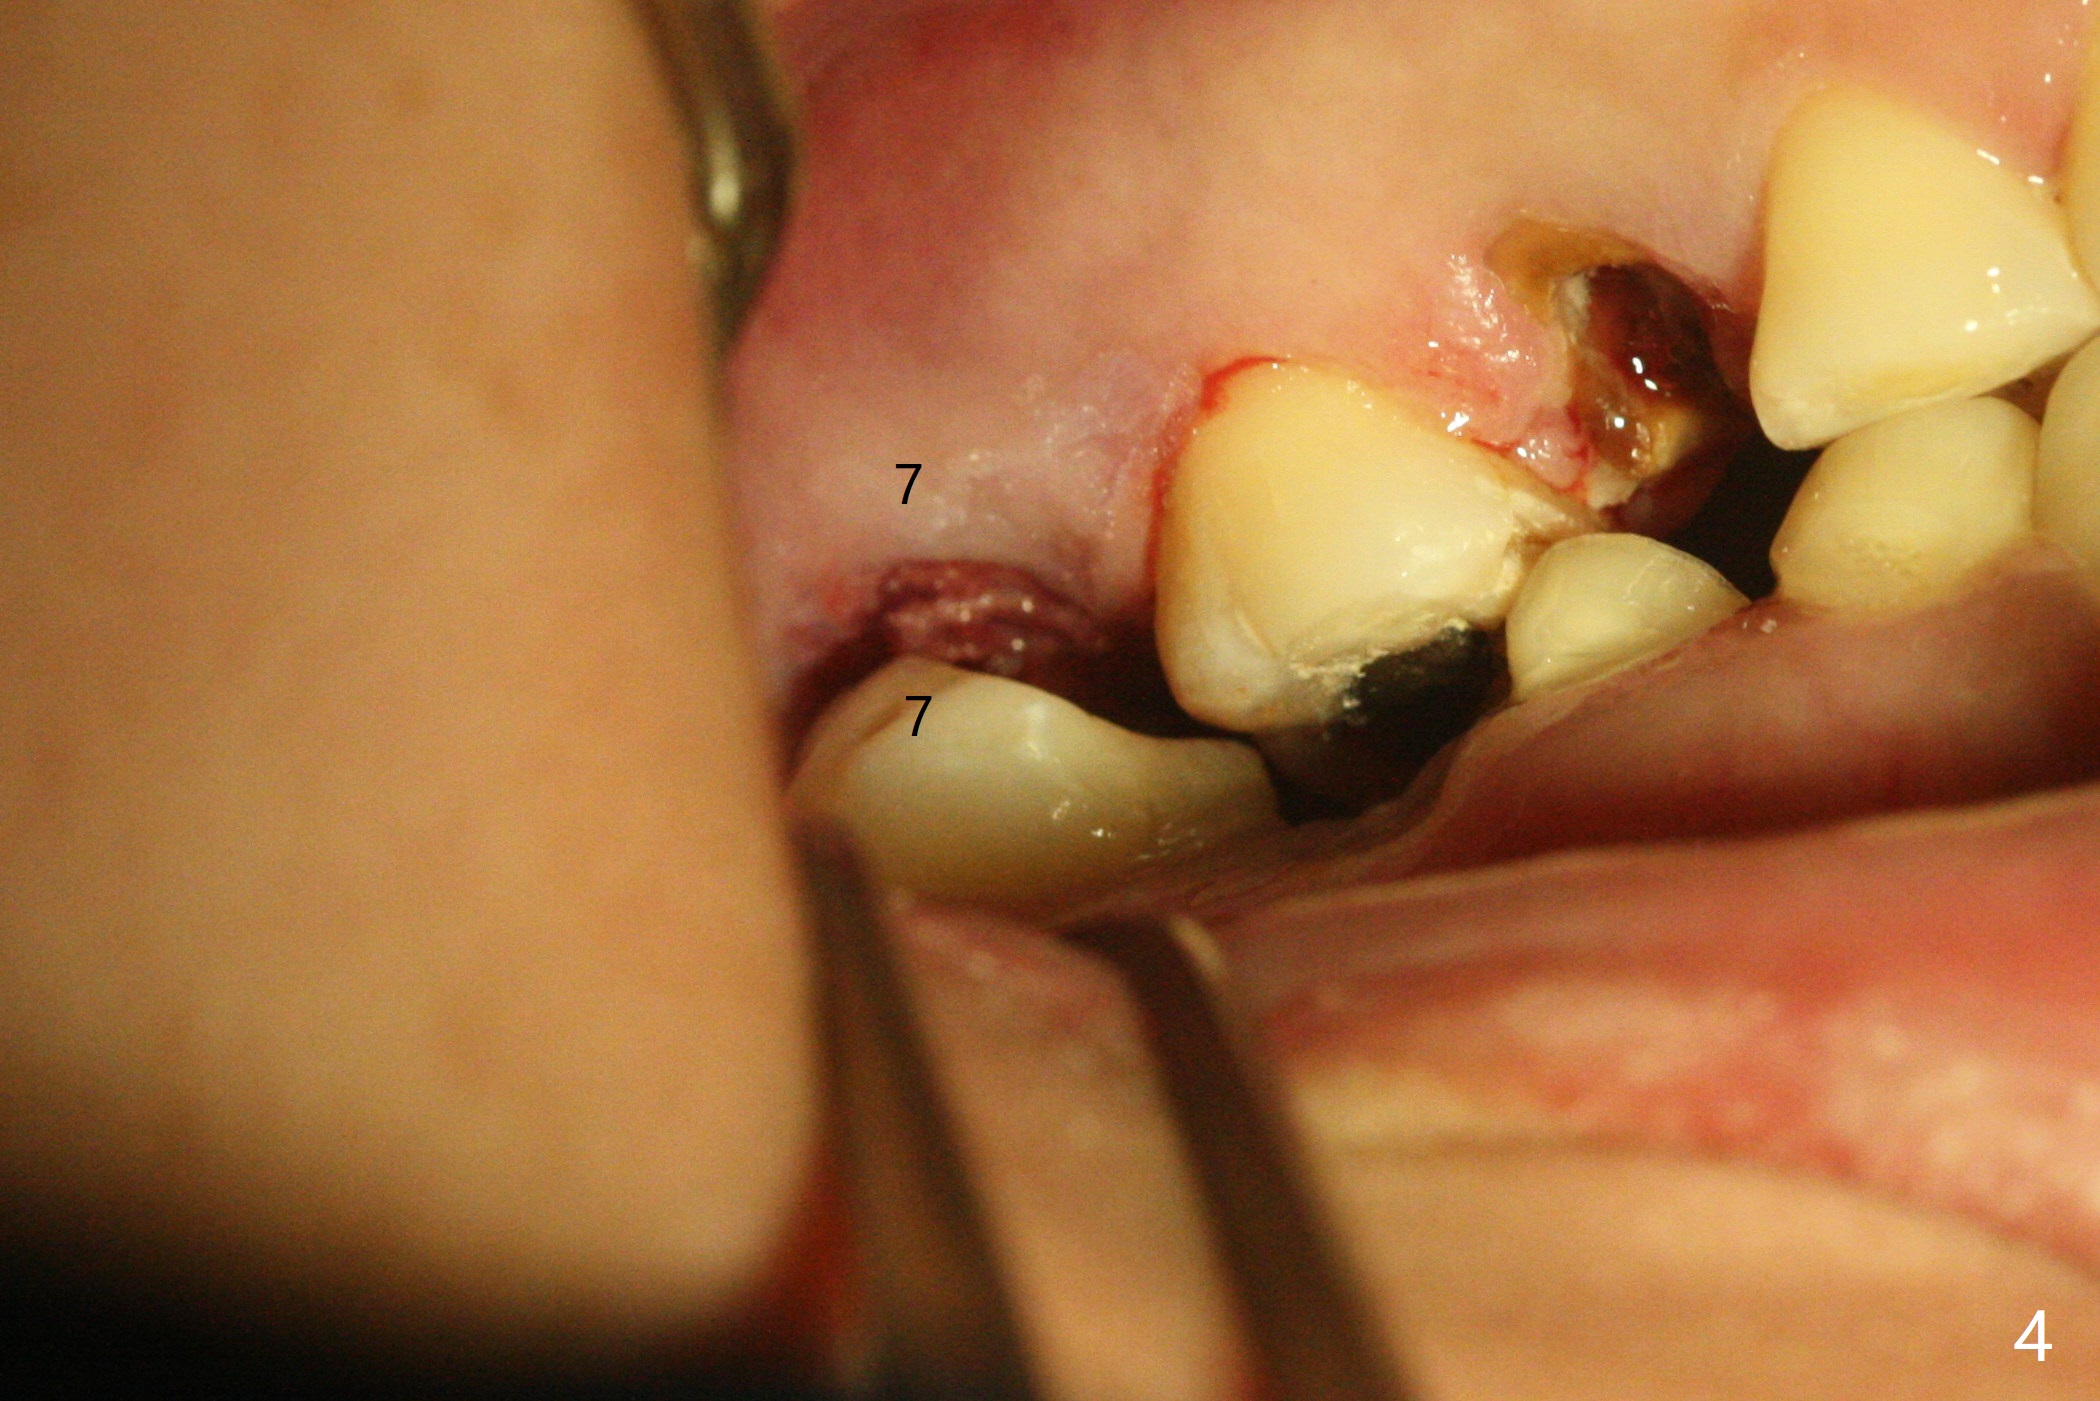

38岁女,牙列不全,咬合塌陷,因右上7疼痛就诊(图一),十分恐惧治疗,虽然残根好像不大,骨粉填入不少(图二:*;使用.5毫升GEM21S,异体骨和合成材料(ß-TCP (beta tricalcium phosphate)),使用不带齿刮匙或者充填器压入牙槽窝。使用GEM Cap(9-12月吸收膜)关闭牙槽窝开口(图三:C),牙周胶水固定膜。由于右下7延申(图一(箭头),四),没有空间放置牙周或者树脂敷料。膜术后4天脱落(加用缝线可以避免早期脱落),7天伤口明显缩小(膜早期脱落好处,图五,与图三对比),白色的骨粉仿佛稳定,所以没有做特殊处理,观察。No Caries GEM21S Xin Wei, DDS, PhD, MS 1st edition 01/26/2021, last revision 02/01/2021